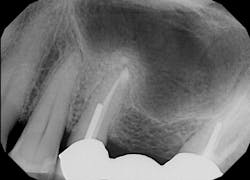

After using a round burnisher and blow test to determine that there was no perforation to the sinus and the membrane was still intact, the laser was used at a spot size of 1.25 mm, on low power mode, and without mist or air to debride the medial superior area of the bony defect. X-rays were taken following immediate placement of bone-graft material to display the site after using Solea to remove bone and granulation tissue (figures 6 and 7). The entire procedure, including the bone graft, took approximately 40 minutes from start to finish.

During post-op visits, final results at the three- and eight-month marks and x-rays taken at eight months revealed optimal outcomes that met the clinical objective (figures 8–10).